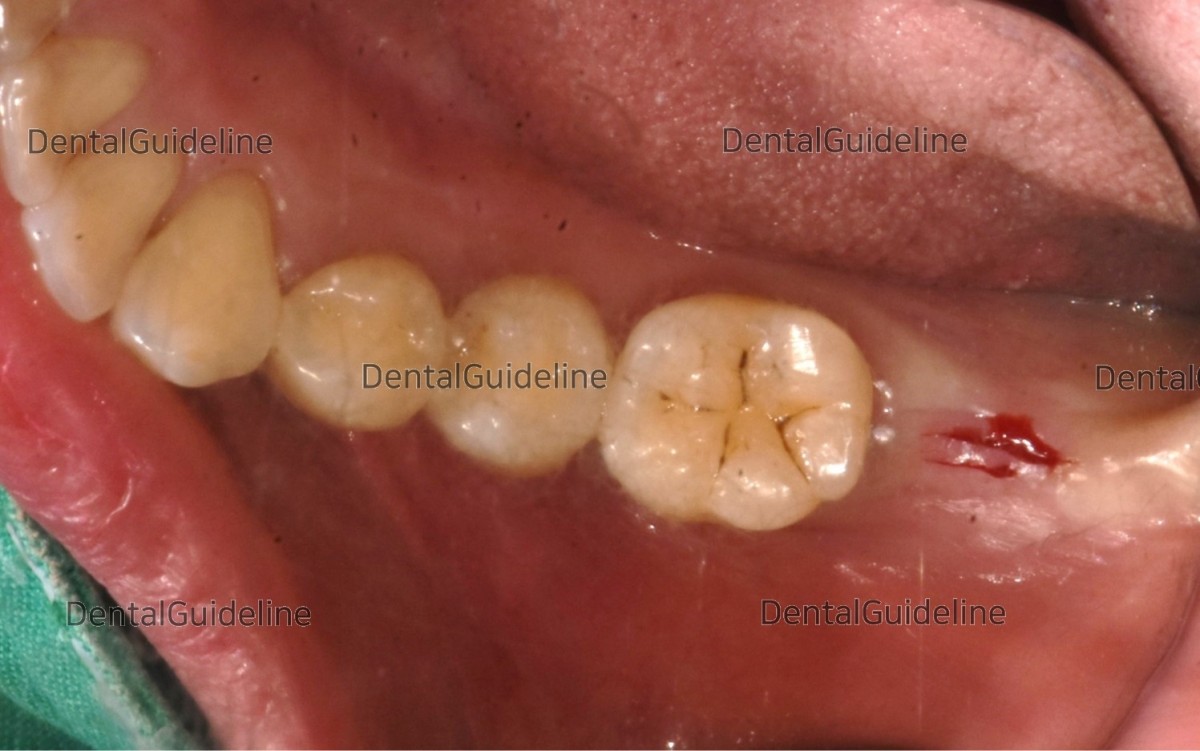

1. Intraoral view before surgery

7. The panoramic radiograph on the day of implant placement.

14. Intraoral photo on the day of impression taking.